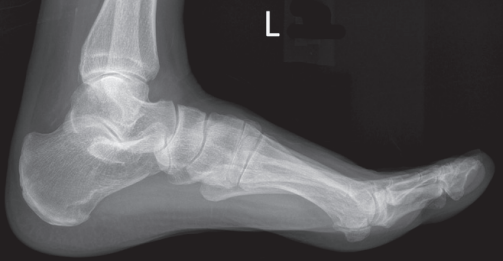

The medial talar dome is demonstrated anterior to the lateral talar dome

Over-rotated/ external rotation

The medial talar dome is demonstrated posterior to the lateral talar dome

Under-rotated/ internal rotation

Medial talar dome is anterior to the lateral dome

Fibula is more posterior

Foot is externally rotated

Medial talor dome is posterior to the lateral dome

Foot is internally rotated

The lateral talar dome is proximal to the medial dome, the height of the medial longitudinal arch appears less than it actually is, and the talocalcaneal joint is narrowed.

Proximal lower leg has been elevated